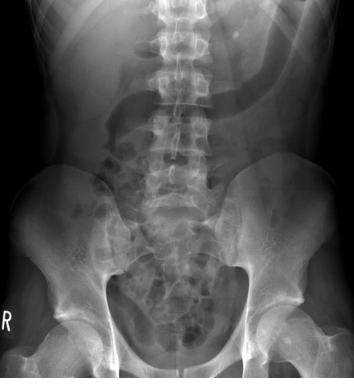

What is the cause of the area of increased density in the pelvis?

Calcified pelvic kidney

Calcified abdominal lymph node

Calcified uterine fibroid

Ingested barium

Calcified adrenal gland